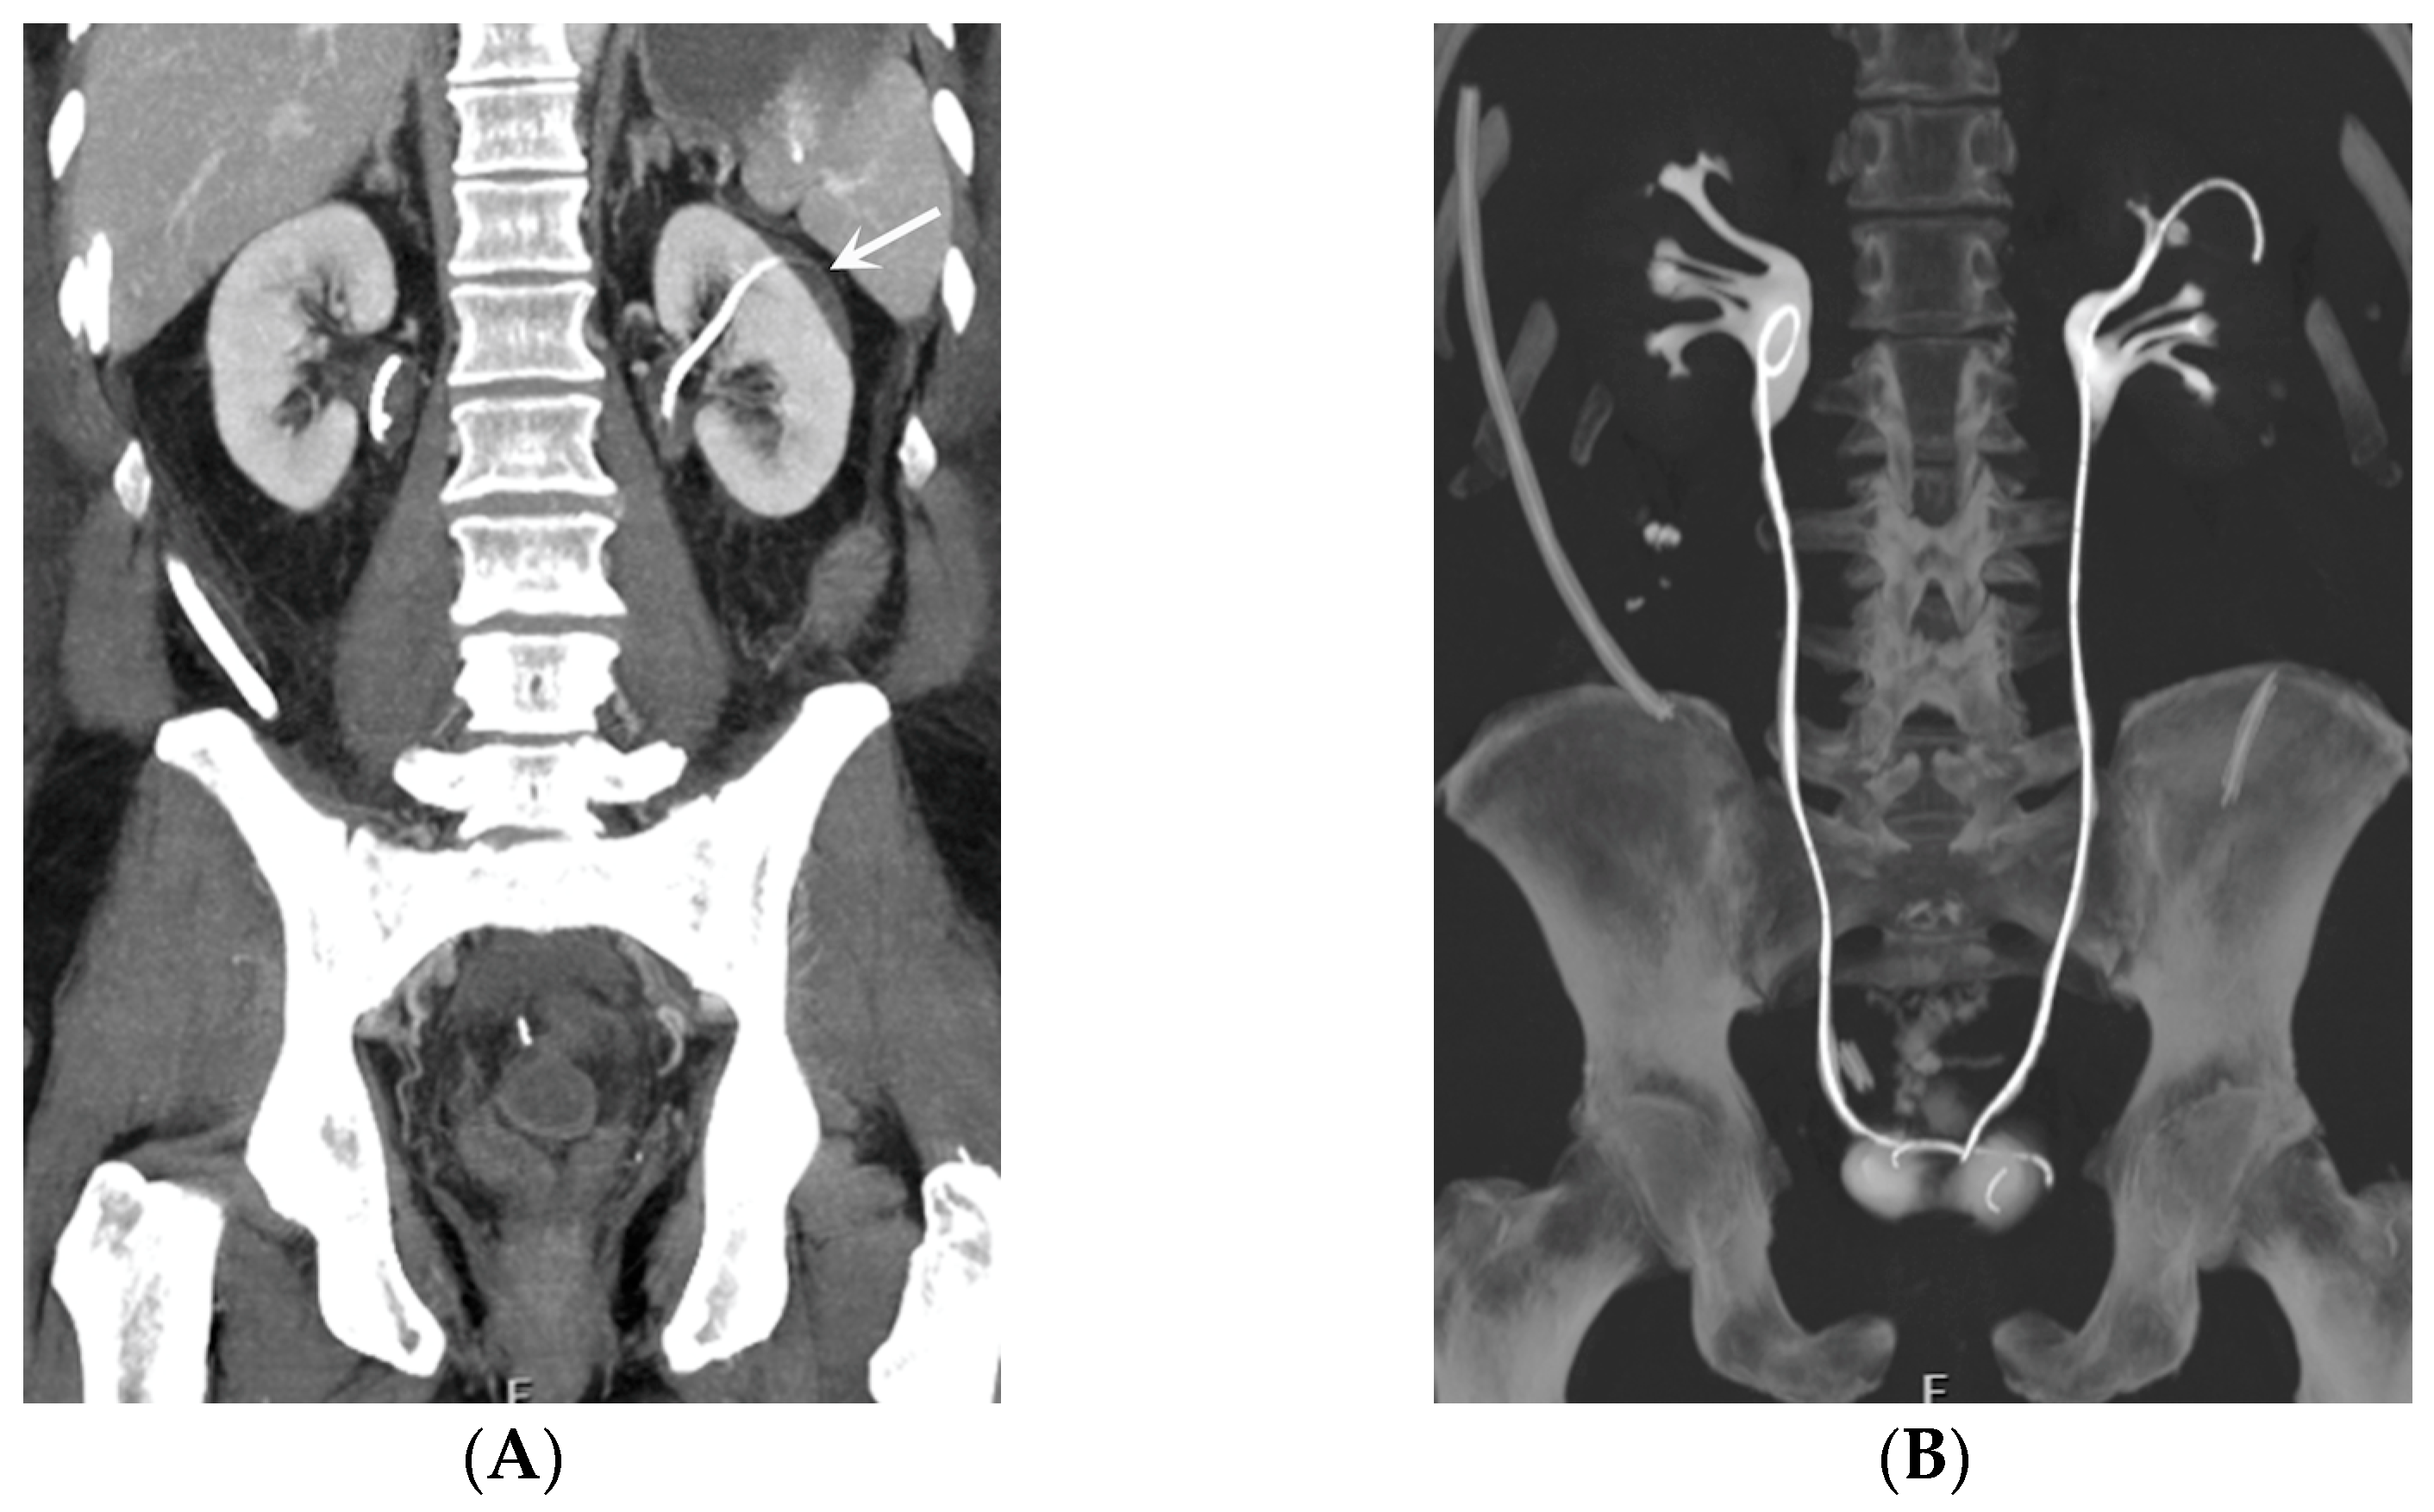

- Malposition: The malposition of a stent is defined as an incorrect position relative to initial placement, while displacement presents a subsequent occurrence in a device that was previously located in the correct position. A stent improperly positioned might assume a sub-pyelic position when the proximal end fails to reach the renal pelvis and a supravesical position when the distal end is detected within the ureter. The origins of this complication predominantly stem from the placement technique, whether it be endoscopy- or fluoroscopy-guided insertion. This underscores the need to verify the accurate positioning of the stent post-placement. Ensuring an adequate length is essential to reduce the occurrence of this complication (Figure 2, Figure 3, Figure 4, Figure 5 and Figure 6) [21,22].